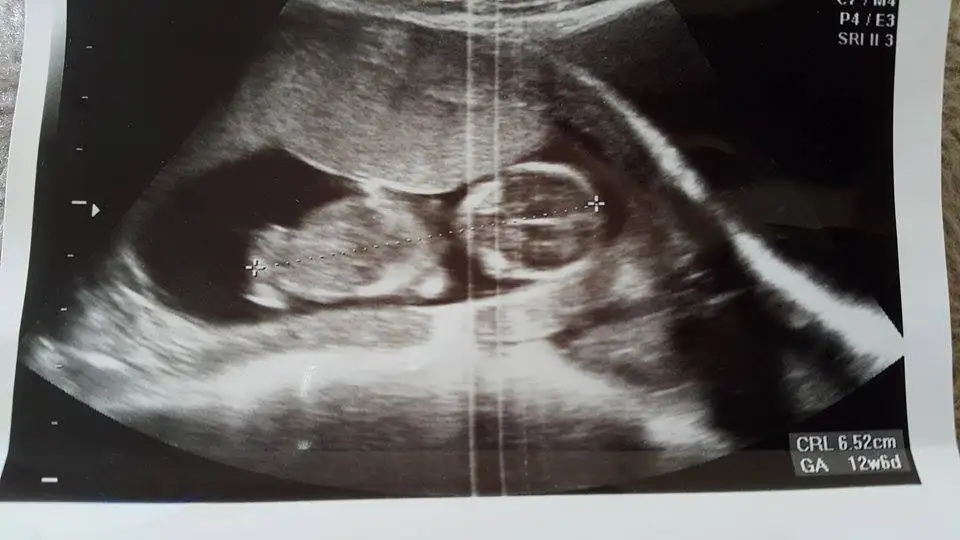

20150430_173613.webp 12+3 sizce cinsiyeti ne olabilor